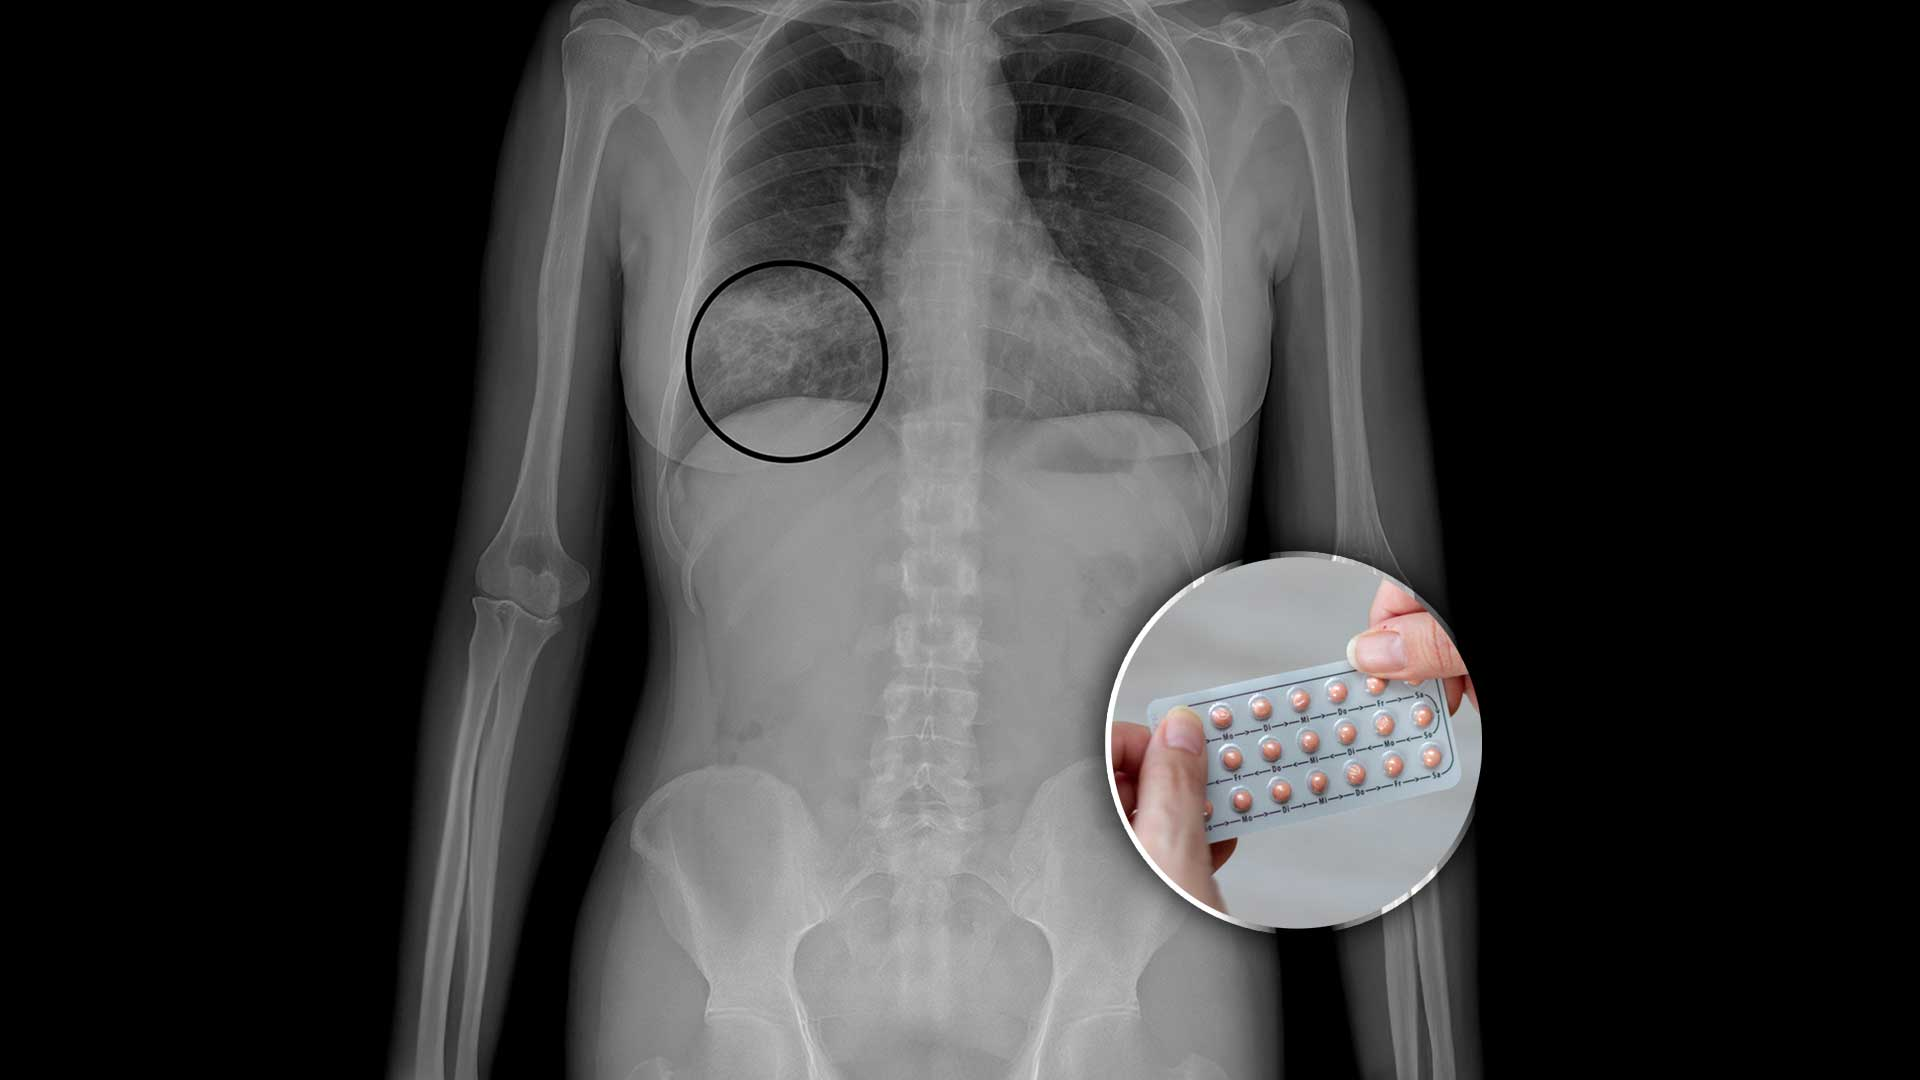

1. Sí aumenta el riesgo de algunos cánceres… pero protege contra otros

La OMS clasifica a los anticonceptivos hormonales combinados como carcinógeno tipo 1.

Esto no significa que causen cáncer automáticamente, sino que existe evidencia científica de que modifican ciertos riesgos.

📌 Aumenta ligeramente el riesgo de:

Cáncer de mama

Cáncer de cuello uterino

📌 Disminuye el riesgo de:

Cáncer de ovario

Cáncer de endometrio

Cáncer de colon